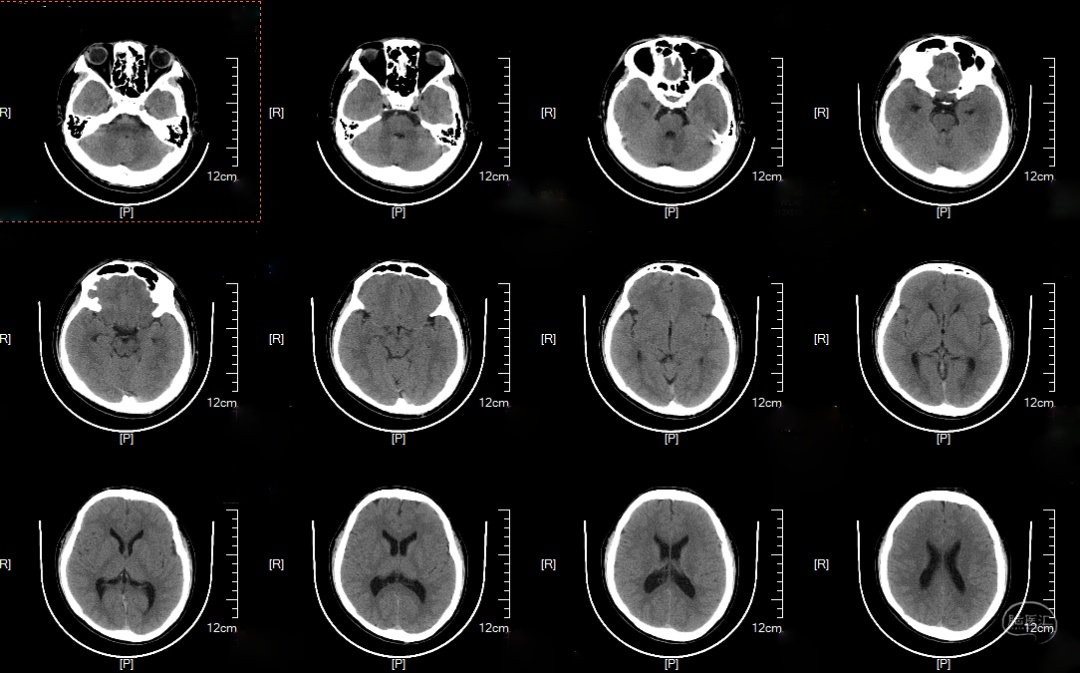

术前影像

头颅CT及MRI: